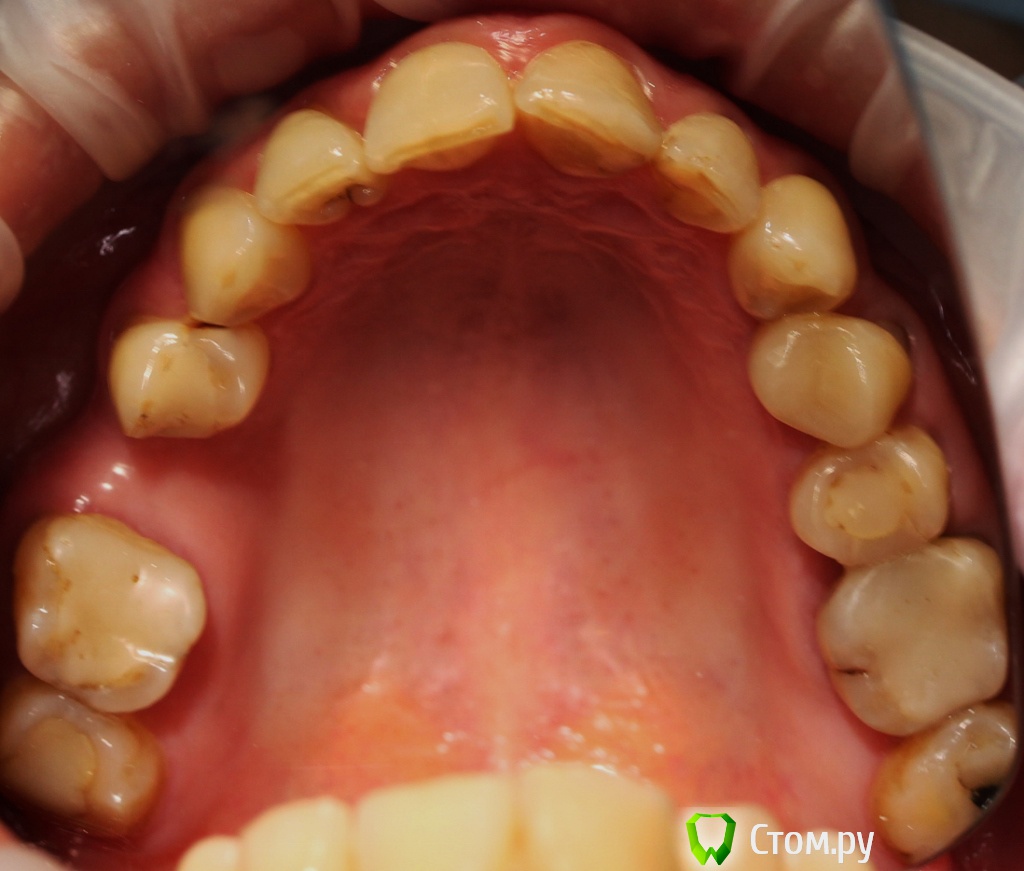

Dr.Sham Опубликовано 21 октября, 2014 Поделиться Опубликовано 21 октября, 2014 (изменено) Пациентка 55 лет с онкологией в прошлом.Аутоиммунный тиреоидит.Хочет красивые зубы, которыми можно жевать.Суставной компонент я не диагностирую, щелчков и посторонних шумов при открывании рта нет. Мышцы без гипертонуса, пальпаторно боли отмечает со стороны крыловидной медиальной и латеральной мышц слева.Фотки. Рентген. КТ пока не делал, хочется сделать с шаблоном, но пока с планом лечения не определились.Брекеты не хочет, каппы хочет, но я не знаю возможности лечения на каппах и доктора ответственного (С-Пб.) Фото: Модели в артикуляторе: ОПТГ Изменено 21 октября, 2014 пользователем Dr.Sham Ссылка на комментарий

Dr.Sham Опубликовано 21 октября, 2014 Автор Поделиться Опубликовано 21 октября, 2014 Доктора, спасибо за ответы, но ощущение, что комментировали одни терапевты.По существу: как можно помочь со скученностью, каковы причины рецессий, клинов на всех зубах, какую окклюзионную схему выстроить? Пролечить или удалить - это все понятно. Пролечили - удалили. В боковых отделах зубо-альвеолярные выдвижения - может и лечить не стоит. Если ортодонтическое лечение на каппах возможно, то кроме скученности в переднем отделе может оно решить проблемы в боковых отделах? Ссылка на комментарий

Дмитрий Никитюк Опубликовано 22 октября, 2014 Поделиться Опубликовано 22 октября, 2014 Доктора, спасибо за ответы, но ощущение, что комментировали одни терапевты.По существу: как можно помочь со скученностью, каковы причины рецессий, клинов на всех зубах, какую окклюзионную схему выстроить? Пролечить или удалить - это все понятно. Пролечили - удалили. В боковых отделах зубо-альвеолярные выдвижения - может и лечить не стоит. Если ортодонтическое лечение на каппах возможно, то кроме скученности в переднем отделе может оно решить проблемы в боковых отделах?Что Вы гадаете всё время? Вы померяли недостаток места во фронтальном отделе н/ч? Сможете Вы его компенсировать сепарацией? Если да, то нет разницы чем ровнять. Сделать интрузию боковых зубов позволит их пародонт? Вы продонтальный зонд брали в руки, а то об этом нет ни слова? Вы можете уже сказать какие зубы удалите, а какие останутся? Вот когда дадите ответы на эти вопросы, можно будет пойти дальше. 1 Ссылка на комментарий

Дмитрий Никитюк Опубликовано 22 октября, 2014 Поделиться Опубликовано 22 октября, 2014 Я не очень понимаю, как измерить недостаток места во фронтальном отделе нижней челюсти. Штангенциркулем.Всё просто на самом деле. Нужно измерять мезио-дистальные размеры резцов, просуммировать их и сравнить с имеющимся расстоянием между клыками (проволочку по форме зубного ряда изгибаете, а потом выпрямляете и к линейке). Про интрузию тоже не знаю, каковы показания/противопоказания для этой манипуляции. Зависит от состояния пародонта. Опора нужна (МИ) + время. По теме: 36, 37 удалены, 38 - кандидат, 16 с трещиной тоже под удаление, 26 - с учетом всех проблем так же на выход. Остаются две верхние семерки - сильно выдвинутые. Вот я и спрашиваю, есть ли смысл их вколачивать? 46 с неадекватной непрямой реставрацией, думаю, под реставрацией безферрульный зуб будет. Так что, предполагаю, что в боковых отделах зубы будут удалены. 38 на удаление.17 возможно ортодонт с пародонтологом дадут добро, но 27 в 28 точно не затолкаете. 46 под вопросом. У меня в практике есть понятие "диагностическое лечение" с целью определения прогноза. Определяем эндопрогноз (прицельный снимок + работа с СКК под микроскопом), пародонтологический прогноз (снимки + зондирование), ортопедический прогноз ( наличие феррула или возможность его создания). Пациент, который дает добро на это, прекрасно понимает, что я могу ему снять старую реставрацию и либо сохранить зуб, либо тут же его удалить (т.е. готов к худшему, но надеется). Естественно пациент платит деньги за это + за лечение или удаление. Ссылка на комментарий